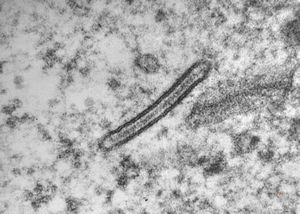

M, 1y. | histiocytosis X (eosinophilic granuloma) - Birbeck body

M, 1y. | histiocytosis X (eosinophilic granuloma) - Birbeck body

M, 7m. | hhistiocytosis X (eosinophilic granuloma) - Birbeck bodies

M,7m. | histiocytosis X (eosinophilic granuloma) … formation of Birbeck body

M, 7m. | histiocytosis X (eosinophilic granuloma) - Birbeck body

M, 1y. | histiocytosis X (eosinophilic granuloma) - Birbeck bodies